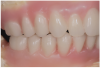

An important advantage of this approach is the ability to simulate bone reduction on the models and verify the presence of 15 mm to 17 mm and 13 mm to 15 mm of required inter-occlusal space for maxillary and mandibular restorations, respectively. This creates a platform for a diagnostic wax-up of the proposed dental rehabilitation and fabrication of wax prosthesis try-ins when necessary. Finally, a modified All-on-4 provisional prosthesis surgical and restorative guide developed by the authors for restoration-driven surgery and simplified restorative procedures is fabricated (Figure 2 through Figure 8).

Fig 3. Desired changes in the incisal plane are marked on the diagnostic models.

Figure 3

Fig 4. Diagnostic wax-up performed after model surgery simulating maxillary tooth extraction. Note that inferior repositioning of the incisal plane helped create the 15 mm to 17 mm inter-occlusal space needed for the maxillary All-on-4 provisional restoration.

Figure 4

Fig 5. Bone reduction model surgery performed in mandibular arch to create 13 mm to 15 mm of inter-occlusal space required for the mandibular All-on-4 provisional restoration.

Figure 5